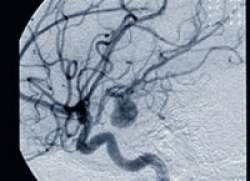

Aneurisma é a dilatação irregular de uma artéria que pode se romper ou trombosar. O rompimento pode levar a uma hemorragia do tipo subaracnóidea. Quando isso ocorre, cerca de 40% dos pacientes morrem e a maior parte dos demais experimenta problemas sérios causados por danos ao cérebro promovidos pelo rápido sangramento.